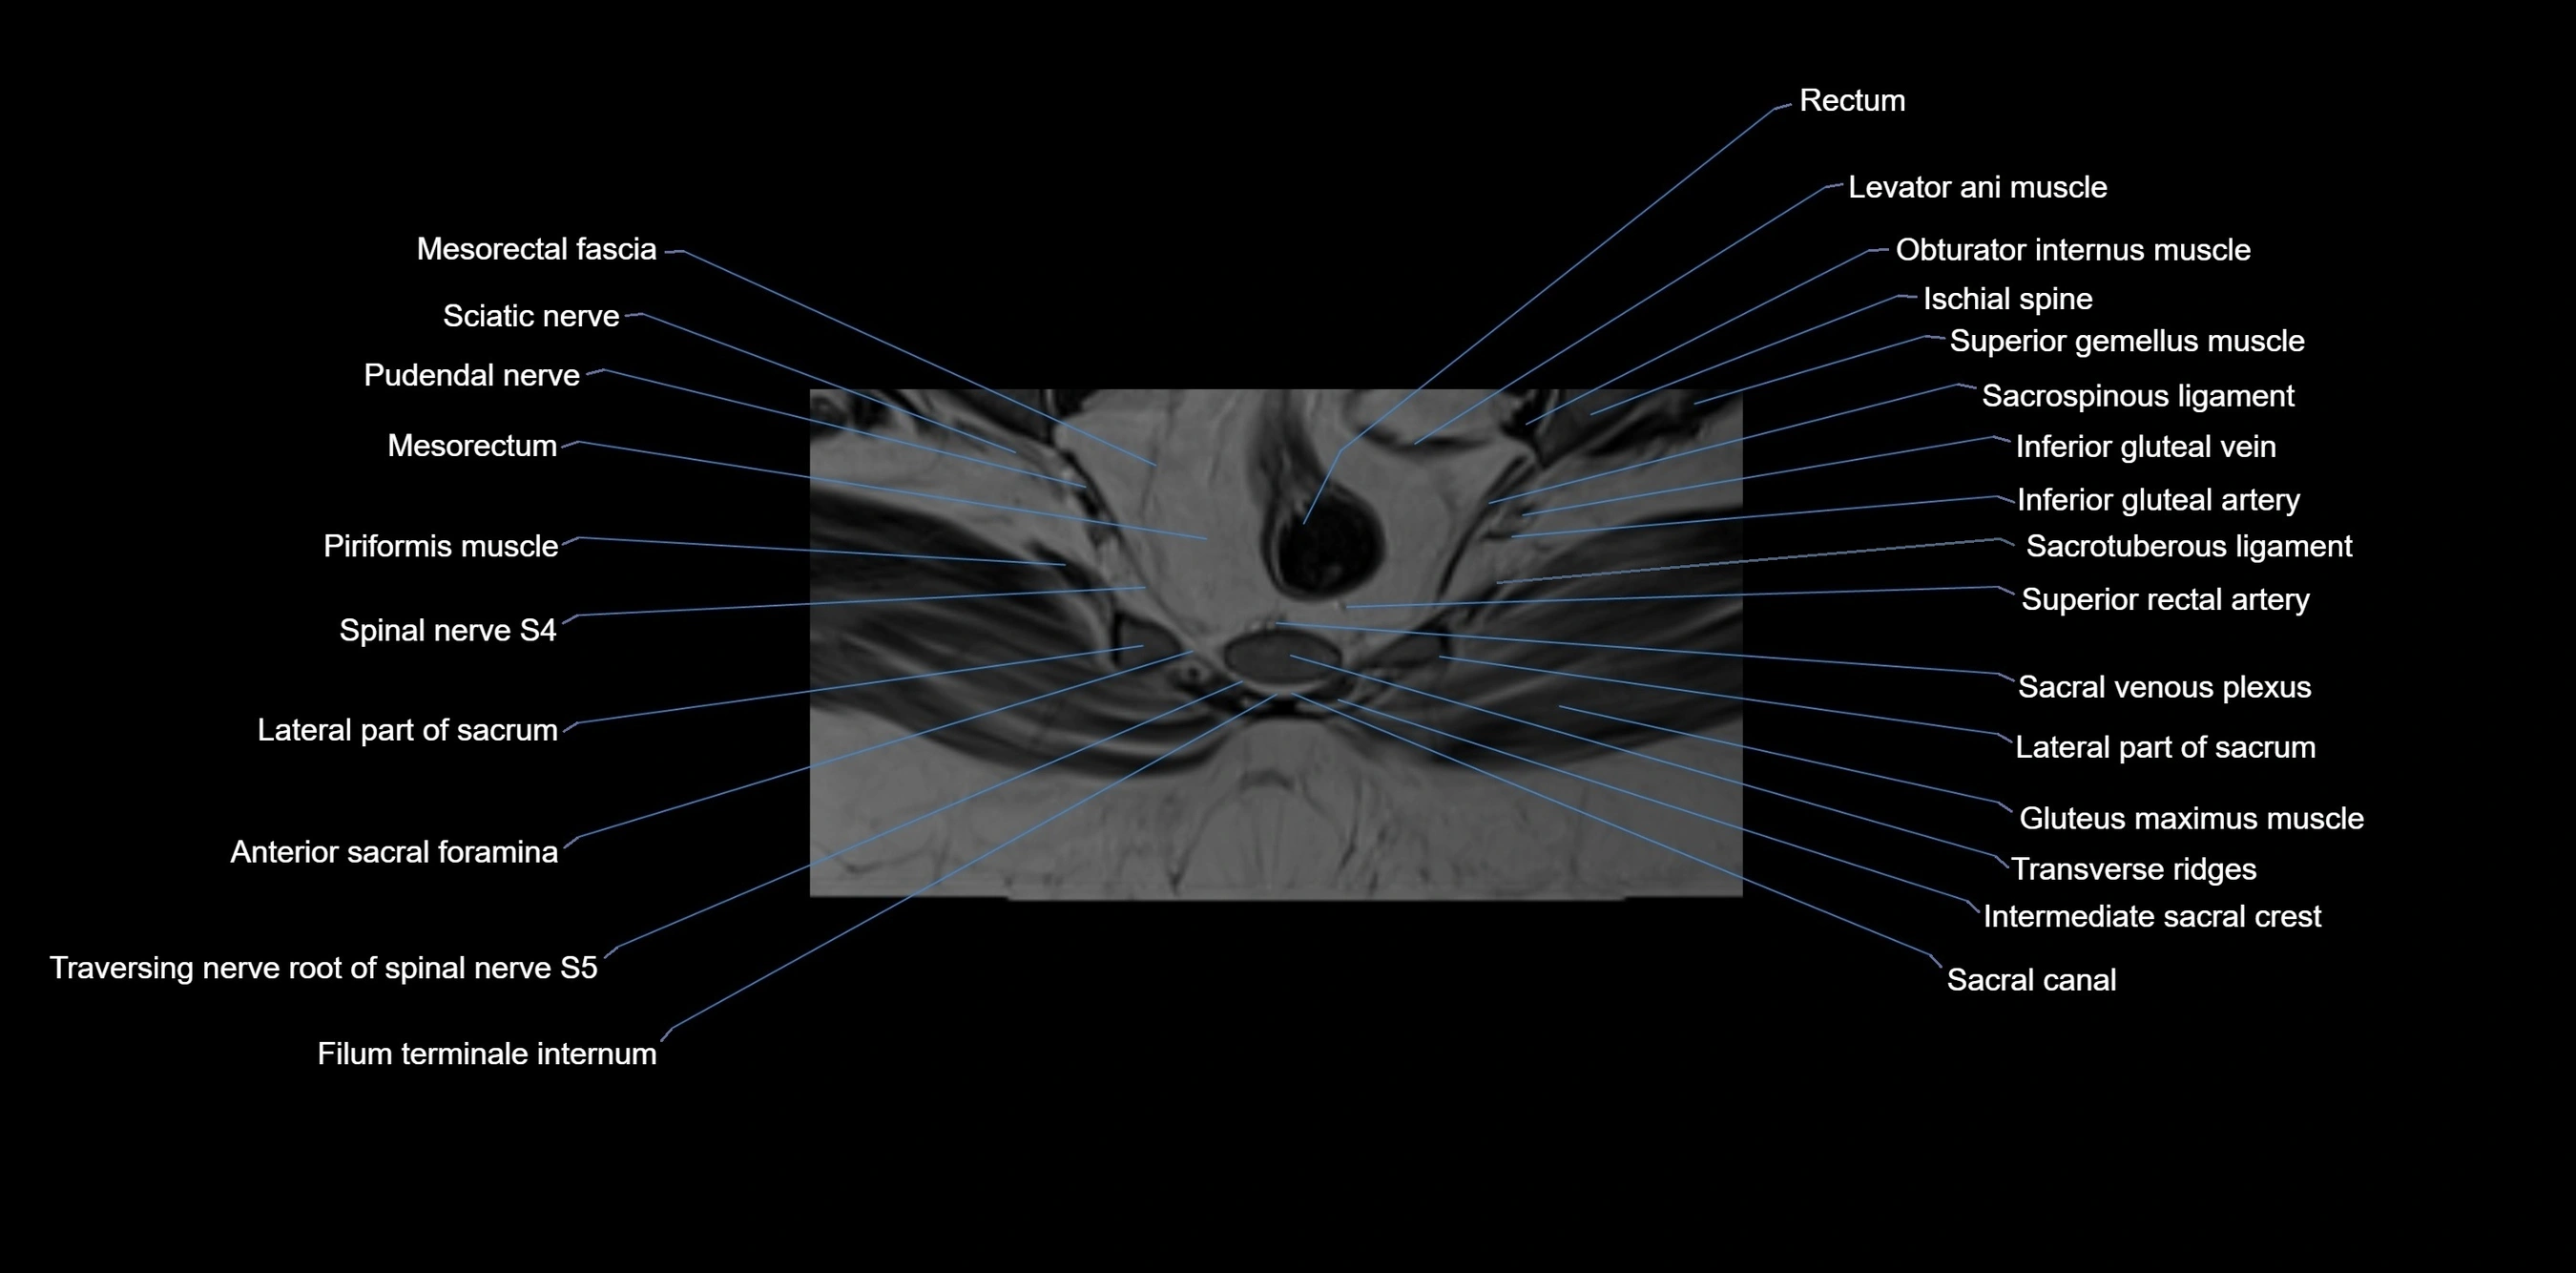

MRI Appearance

T1-weighted images:

• Cortical bone appears very low signal (dark); marrow shows intermediate signal

• Iliac fossa fat is bright against low-signal cortex

T2-weighted images:

• Cortical bone remains dark

• Marrow signal varies depending on fat content; edema or tumor shows hyperintensity

STIR:

• Suppresses fat, making bone marrow edema, fractures, or infiltrative lesions appear bright

• Excellent for trauma, sacroiliitis, and metastatic evaluation

T1 Fat-Saturated (Pre-contrast):

• Marrow: intermediate signal, fat suppressed

• Useful for detecting subtle marrow abnormalities adjacent to iliac cortex

T1 Fat-Saturated Post-Contrast (Gadolinium):

• Enhances vascularized structures, marrow pathology, tumors, and inflammatory changes

• Highlights soft tissue or bone invasion in pelvic neoplasms

MRI Non-Contrast 3D Imaging:

• Provides 3D morphology of iliac wing, crest, and articulations

• Used in preoperative planning for pelvic surgery and trauma reconstruction

MRI image

image